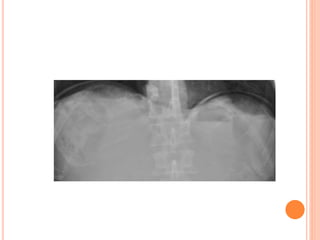

ABDOMINAL RADIOGRAPHY IN EMERGENCY